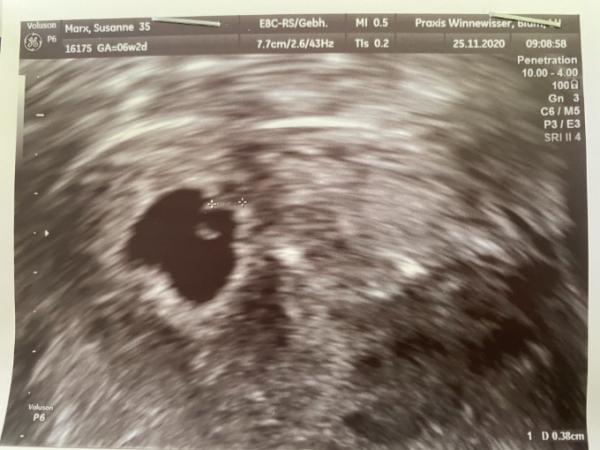

Hallo zusammen, ich war heute beim ersten Ultraschall und bin ganz glücklich, dass ich das kleine Herzchen habe blubbern sehen können. Alles gut also was das anbetrifft. Die Ärztin sagte nun allerdings, dass das Baby sich rechts in der Ecke eingenistet hat, da könnte es eng werden und die Haut sei da auch dünner. Es liegt in der Höhle aber eher nach links wo es hin soll. Ich schätze der Bereich zwischen Falsch und richtig liegt bei 1 cm. Kontrolle ist kommenden Donnerstag. Kennt das jemand? Liebe Grüße Neo

Bild zu In ungünstige Ecke eingenistet - Forum für Juli - Mamis

Wenn ich ehrlich bin habe ich noch nie so einen Unfug gehört schaut ganz normal aus das Bild.